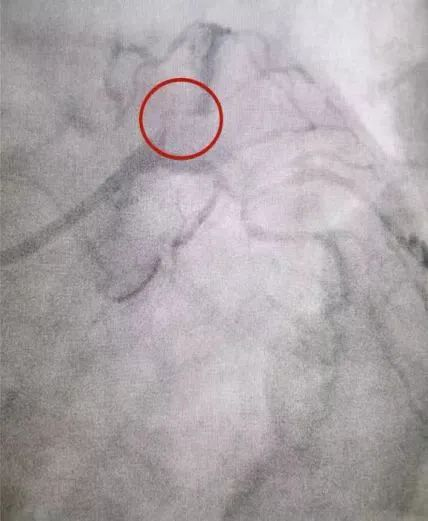

心血管内科是我院的重点专科,我院院长何鹏程也是心血管领域的知名专家,尤其在心血管介入手术方面具有很高的知名度,手术病例多次获邀在国内外顶级学术会议上交流分享。我院在心血管领域方面的实力,吸引众多异地患者前来就医,其中就包括一名来自海南省的患者。林某是一名冠心病患者,曾在海南当地尝试介入治疗开通堵塞的心脏血管但未成功,在海南省心血管同行的举荐下,不远千里专程乘飞机慕名前来我院就医。何鹏程精心准备,带领团队克服了入路血管迂曲、病变血管迂曲、病变血管钙化等冠脉介入手术中的层层挑战,成功为患者开通了前降支病变血管,困扰患者多年的心绞痛症状马上缓解,并很快康复出院。离院之际,林某及其家属对我院的医疗技术和服务水平表达了真心的感谢,表示这趟超越千里的求医之旅达成了他们的期望,取得了良好的效果。

术前:冠状动脉严重狭窄